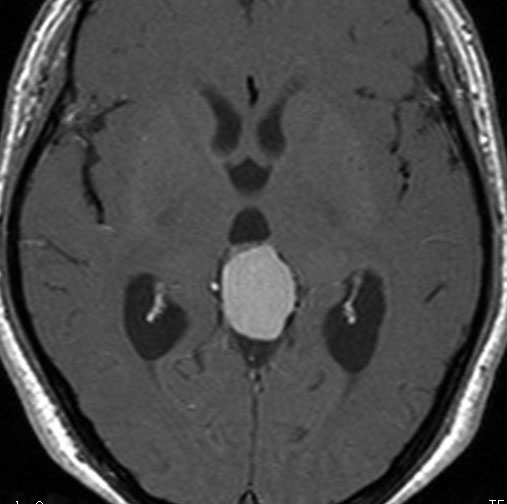

静脈洞交会髄膜腫 meningioma of the confluence of sinuses

若い女性に偶然発見されたものです。直静脈洞と静脈洞交会の接合部あたりに発生したもので,静脈洞はほぼ閉塞に近い所見でした。しかし,この部分の静脈洞は,テント硬静脈側副路が発達することがあるので,硬膜を含めた積極的な摘出をすることは絶対にできません。もしほんの少しでも流れがある直静脈洞を閉塞させると短時間に脳死になるような脳静脈圧亢進が生じる可能性があるからです。静脈洞内に少し取り残して(右下の矢印)手術を終了しました。手術後には定位放射線治療を行って再増大を防ぎます,